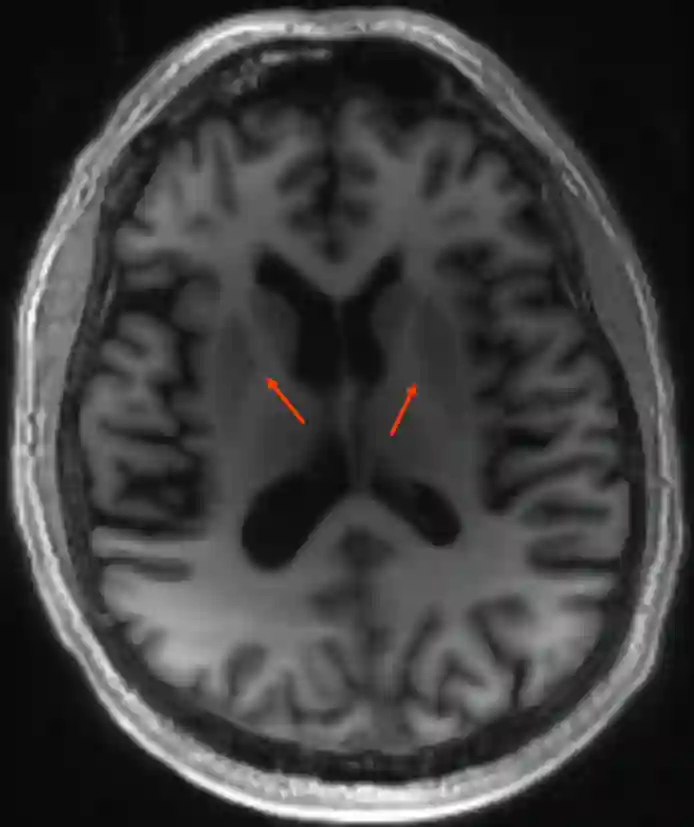

Die Capsula interna ist ist eine anatomische Struktur des Großhirns.

Die Capsula interna wird innen vom Nucleus caudatus und vom Thalamus, außen vom Putamen und vom Pallidum begrenzt. Als wichtigste Faserverbindung läuft der Tractus corticospinalis innerhalb der Capsula interna in Richtung Hirnstamm.

Bildgebung

Die Capsula interna kann in der MRT-Bildgebung dargestellt werden.